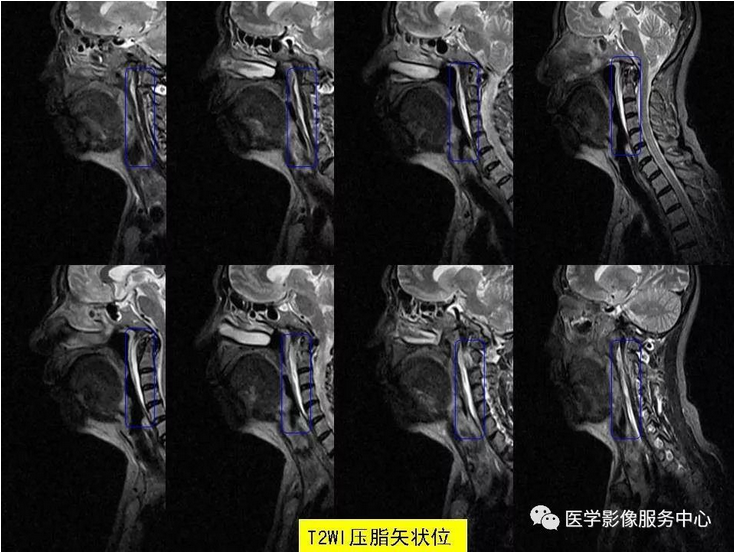

颈椎前缘的条状高信号影,终于知道是什么啦~~

颈项疼痛是临床常见症状,最常见的原因就是颈椎病,包括颈椎骨质增生,颈椎间孔狭窄、颈间盘膨隆突出等表现,综合运用DR、CT、MRI这些影像检查方法,比较容易做出诊断,除此之外,引起颈项疼痛,还有比较少见的原因,不为影像诊断及临床医师所熟知,接下来我们看看下面的2个病例,比较少见的颈长肌肌腱炎。

颈长肌肌腱炎,是以颈项疼痛为主要临床表现的一种疾病,因颈长肌前方毗邻食道及咽部,常常伴发咽部疼痛和吞咽疼痛,临床及影像科医生对其认识较少,常易与其它引起颈项疼痛的疾病混淆 。

其病因为羟磷灰石结晶沉积于颈长肌上斜肌引起的炎性反应,以刺激组织渗出为主。羟磷灰石结晶沉积机制尚不十分明确,可能与损伤、组织坏死和炎症等因素相关。